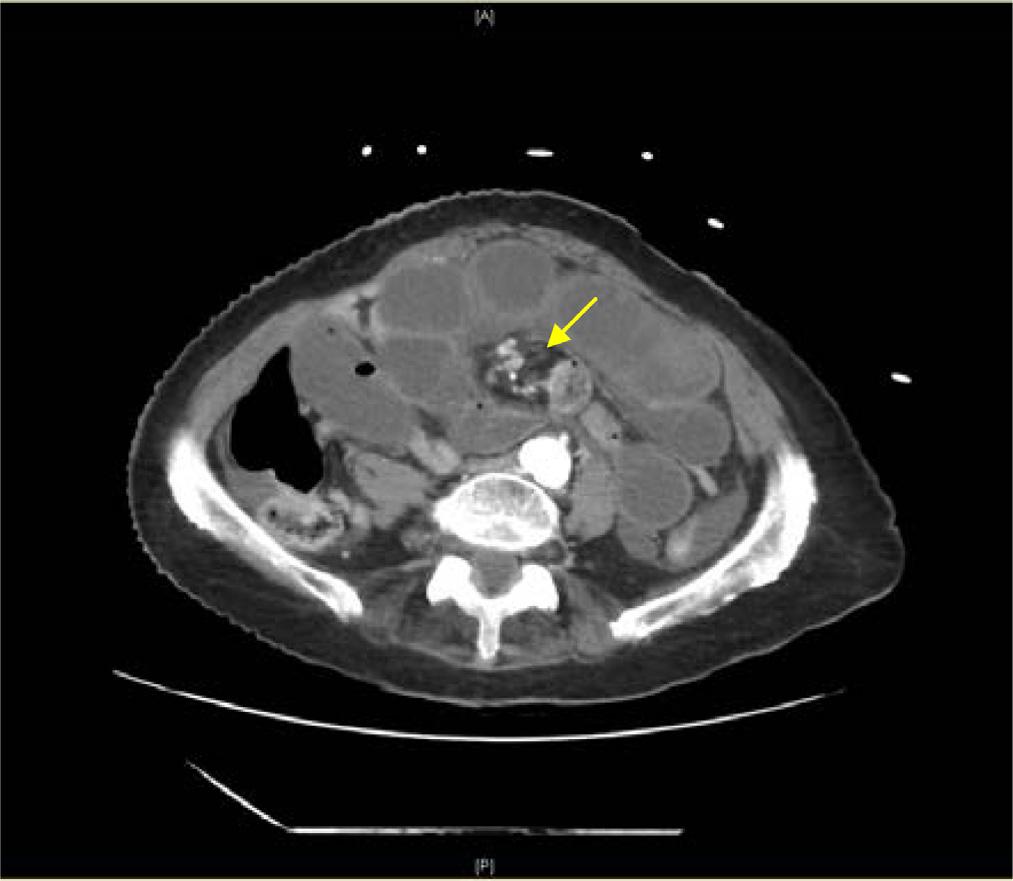

Image. Computedtomographyabdomenwithintravenouscontrast demonstratingdilated, fluid-filledloopsofsmallbowelandapattern ofswirlingmesentericvesselscalledthewhirlpoolsign(arrow).

Onpresentationthepatientwasinnoacutedistressbut wasclammyandtachycardicatarateof118beatsper minute.Onexam,herabdomenwasdiffuselytenderwithout distentionorperitonealsigns.Shehadanelevatedwhite bloodcellcountat17 × 103 permicroliter(K/μL)(reference range4.5–11.0K/μL),anINRof5.5,andalacticacidof 3.7millimolesperliter(mmol/L)(0.4–2.0mmol/L).An abdomenandpelvisCTwithintravenous(IV)contrast showed findingssuspiciousforclosedloop,smallbowel obstruction.TheCTalsodemonstratedevidenceofswirling ofthemesentericroot,knownasawhirlpoolsign(Image, Video).The findingsofthewhirlpoolsignonCTsuggested mesentericvolvulusasthecauseofherbowelobstructionand promptedemergentsurgicalconsultation.

pathology.However,radiographsareofteninconclusivein midgutvolvulusbecauseevenapositive “doublebubble” signindicatingasmallbowelobstructiondoesnotruleouta concomitantmidgutvolvulus.7 Computedtomographywith IVcontrastgivesmuchgreaterdetailoftheabdomenandcan provideevidencesuggestiveofamidgutvolvulus.ClassicCT imaging findingsincludeawhirlpoolsignoftwisted mesentery,malrotatedbowelconfiguration,inverted superiormesentericarteryandsuperiormesentericvein relationship,bowelobstruction,andfree fluid/freegasin advancedcases.8 ThewhirlpoolsignseenonCTrepresents themesenteryandsuperiormesentericveinwrapping aroundthesuperiormesentericarteryina counterclockwisedirection.